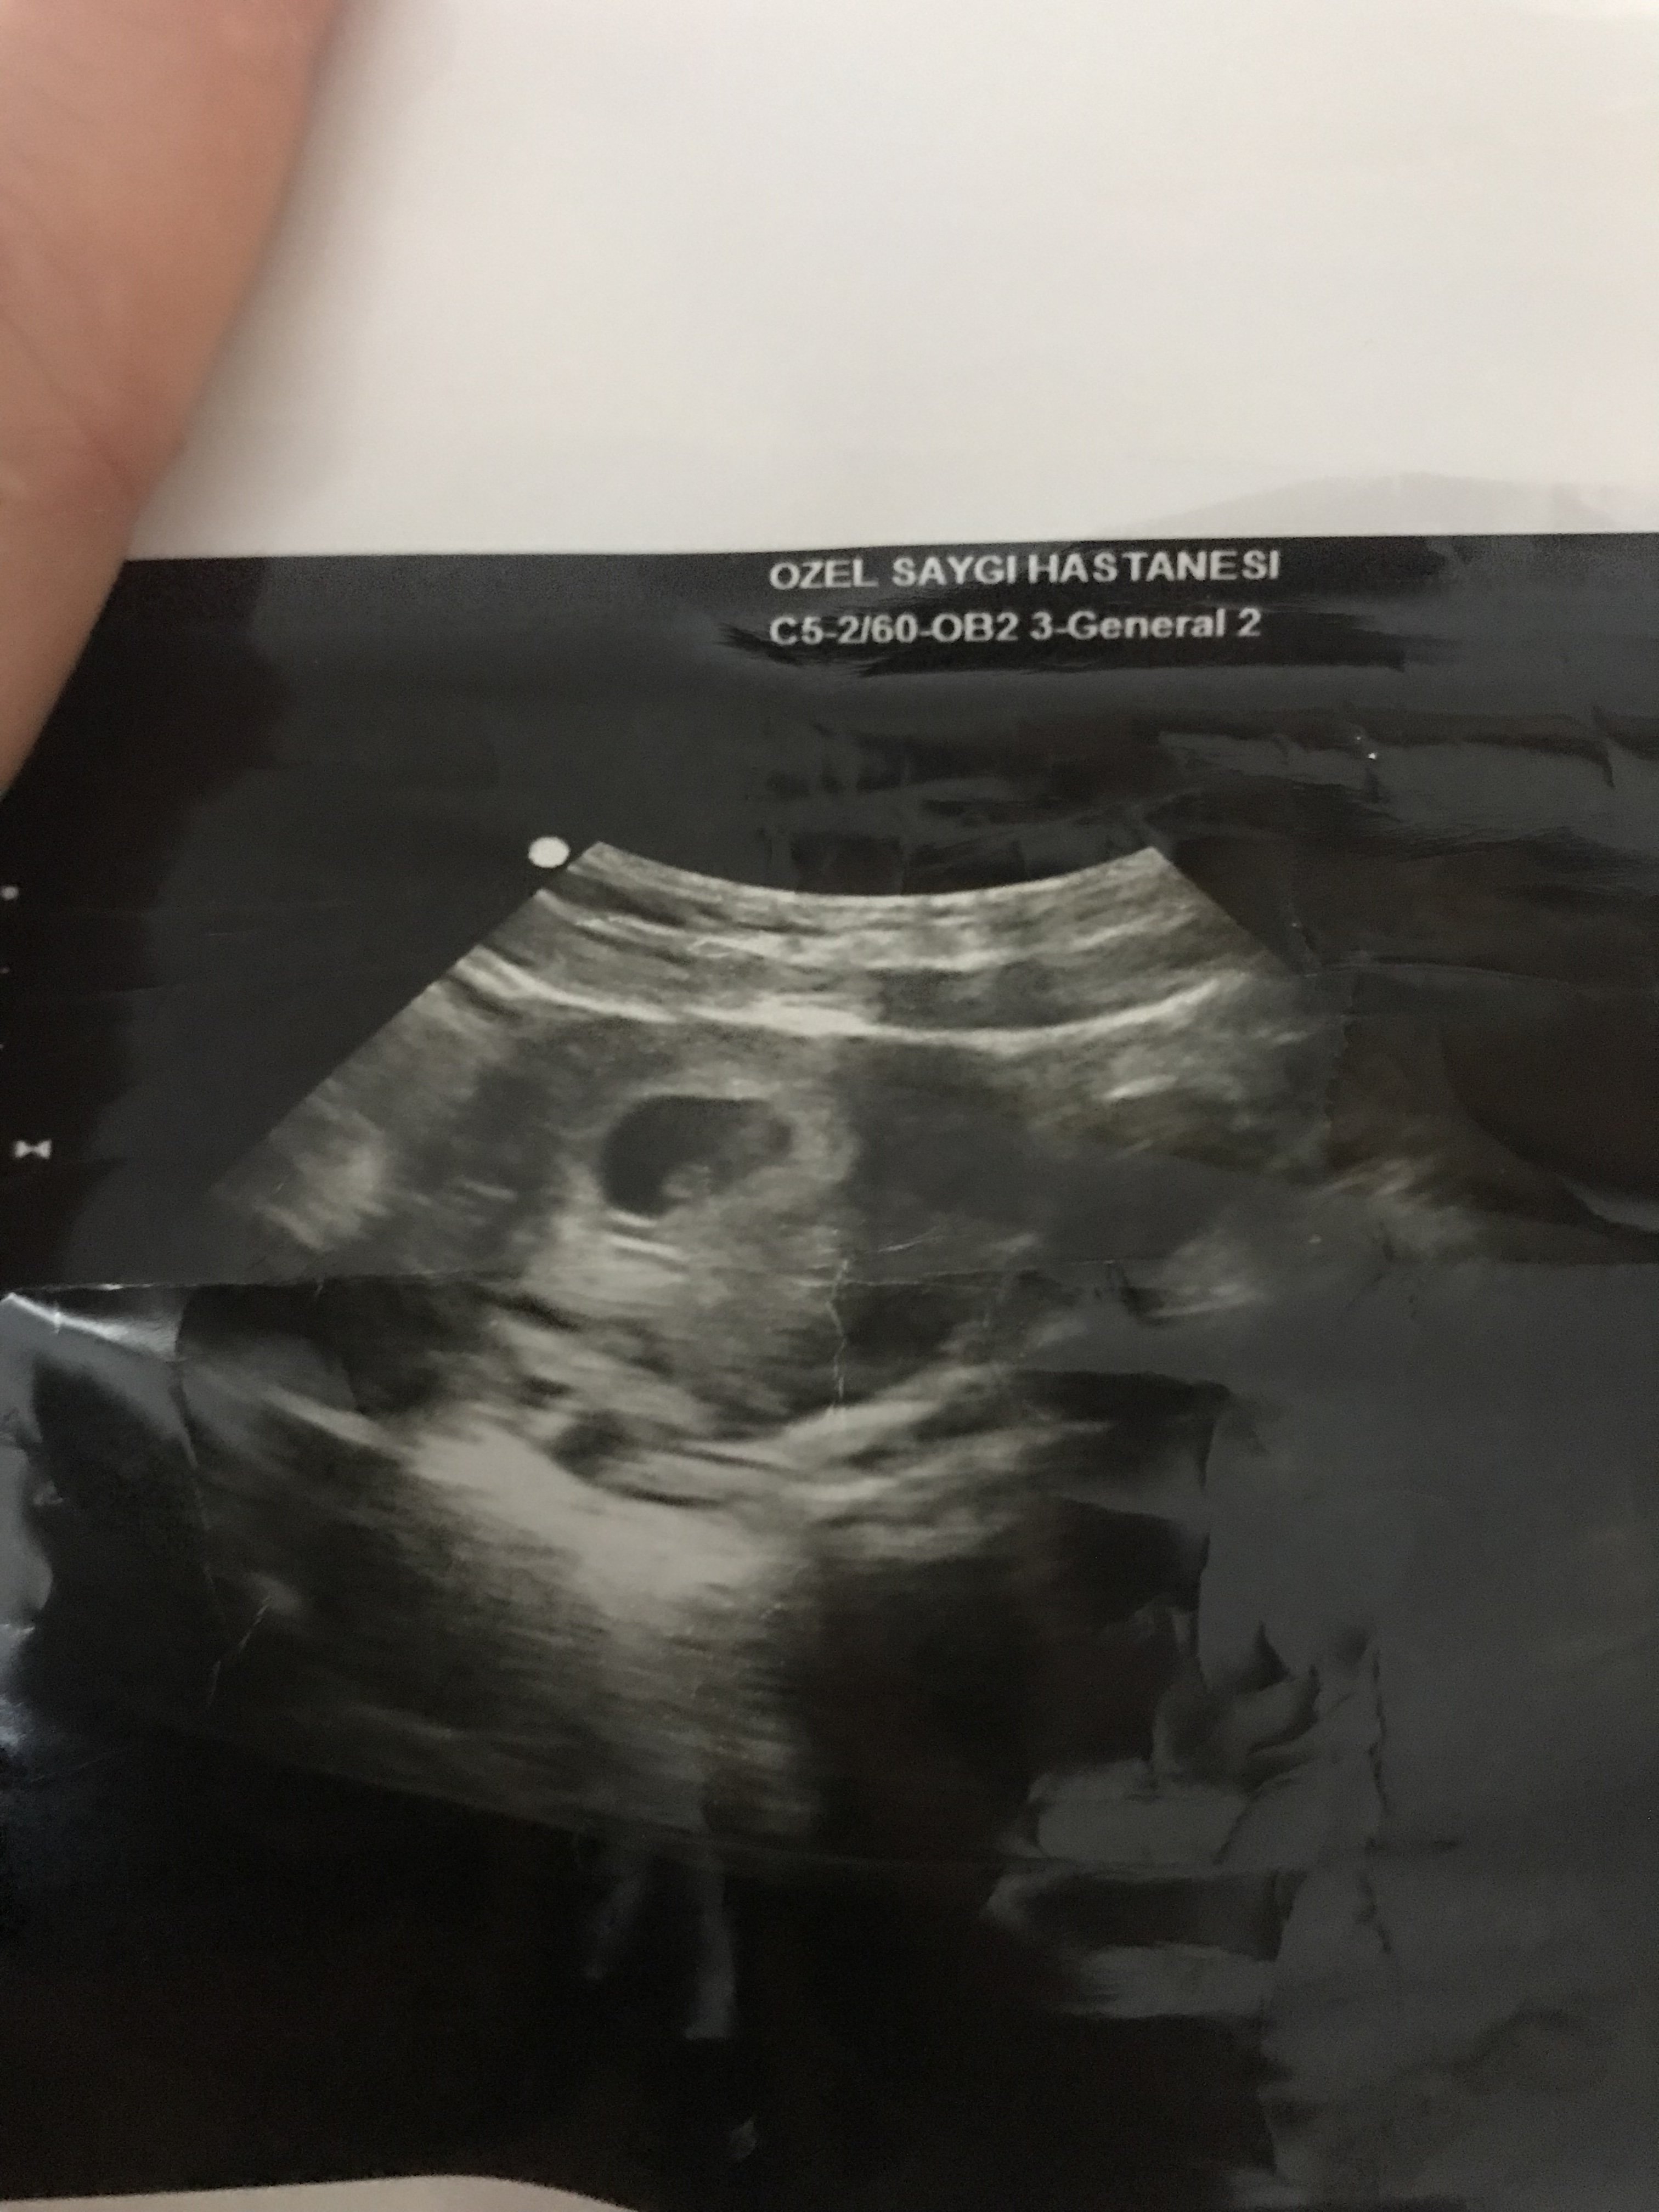

Merhaba .Bunlarda 6+4 günlük usg fotolarım.Ramzi teorisine göre de yorum yapabilir misiniz

Selamlar, bu yuvarlak kese olan bölümü yakın atar mısınız tam anlamı ile yorum yapamıyoruz görmediğimiz için